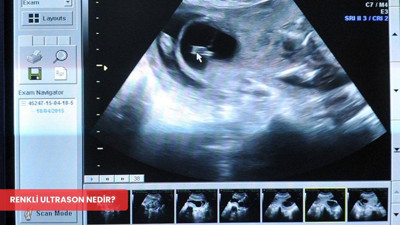

Renkli ultrason neden tercih ediliyor, hangi hastalıkların teşhisinde avantaj sağlıyor ve gebelik sürecinde nasıl bir rol oynuyor? İşte tüm detaylar...